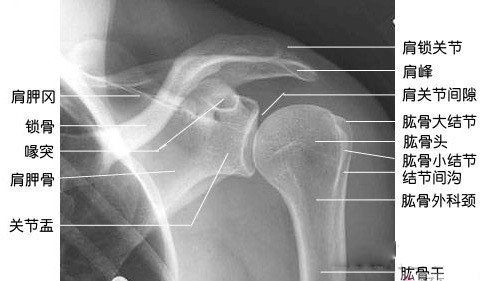

肩关节:事实上,肩关节具有三个旋转自由度,但每个方向的运动范围有限且不一致。大家可以参考下面这张X光片pg赏金女王单机版试玩平台,确实是一个球铰链接。